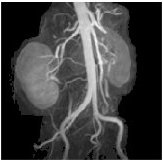

Figure 2. MRA renals with ASSET

- for breath hold angiography studies where a loss of SNR is not a consideration. ASSET is available with TRICKS to enhance the temporal resolution by doubling it. Since there is no multi-breath hold calibration, be sure to match the breath hold (inhale versus exhale) between the calibration scan and accelerated scans to avoid misregistration artifacts.